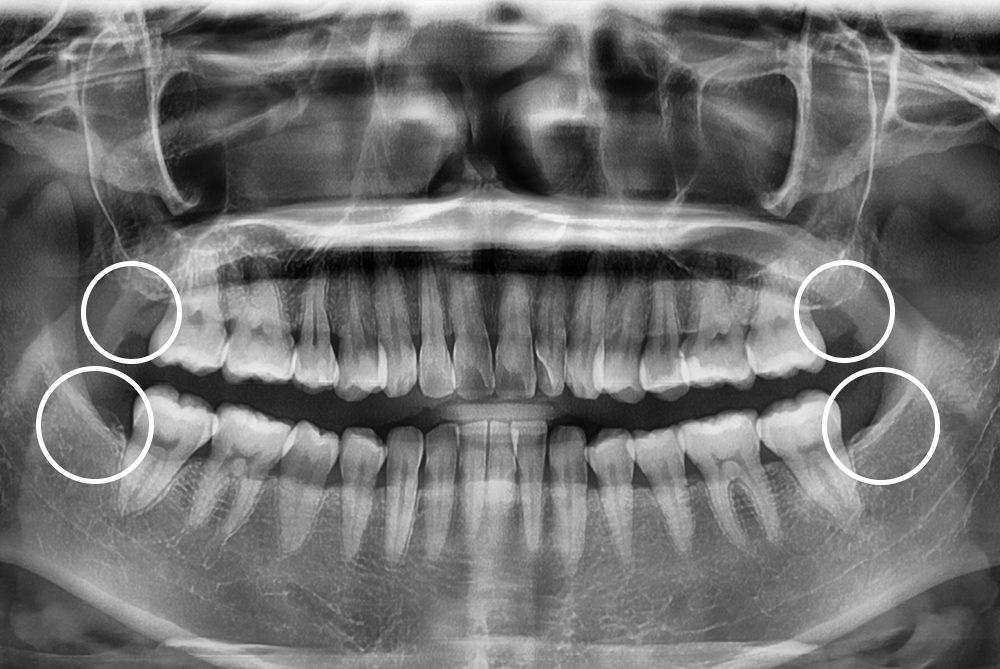

[사랑니] 매복 사랑니 발치

치료후 : 2021-12-23

세종치과는 구강악안면외과학 박사이신 원장님이 발치하는 치과입니다.